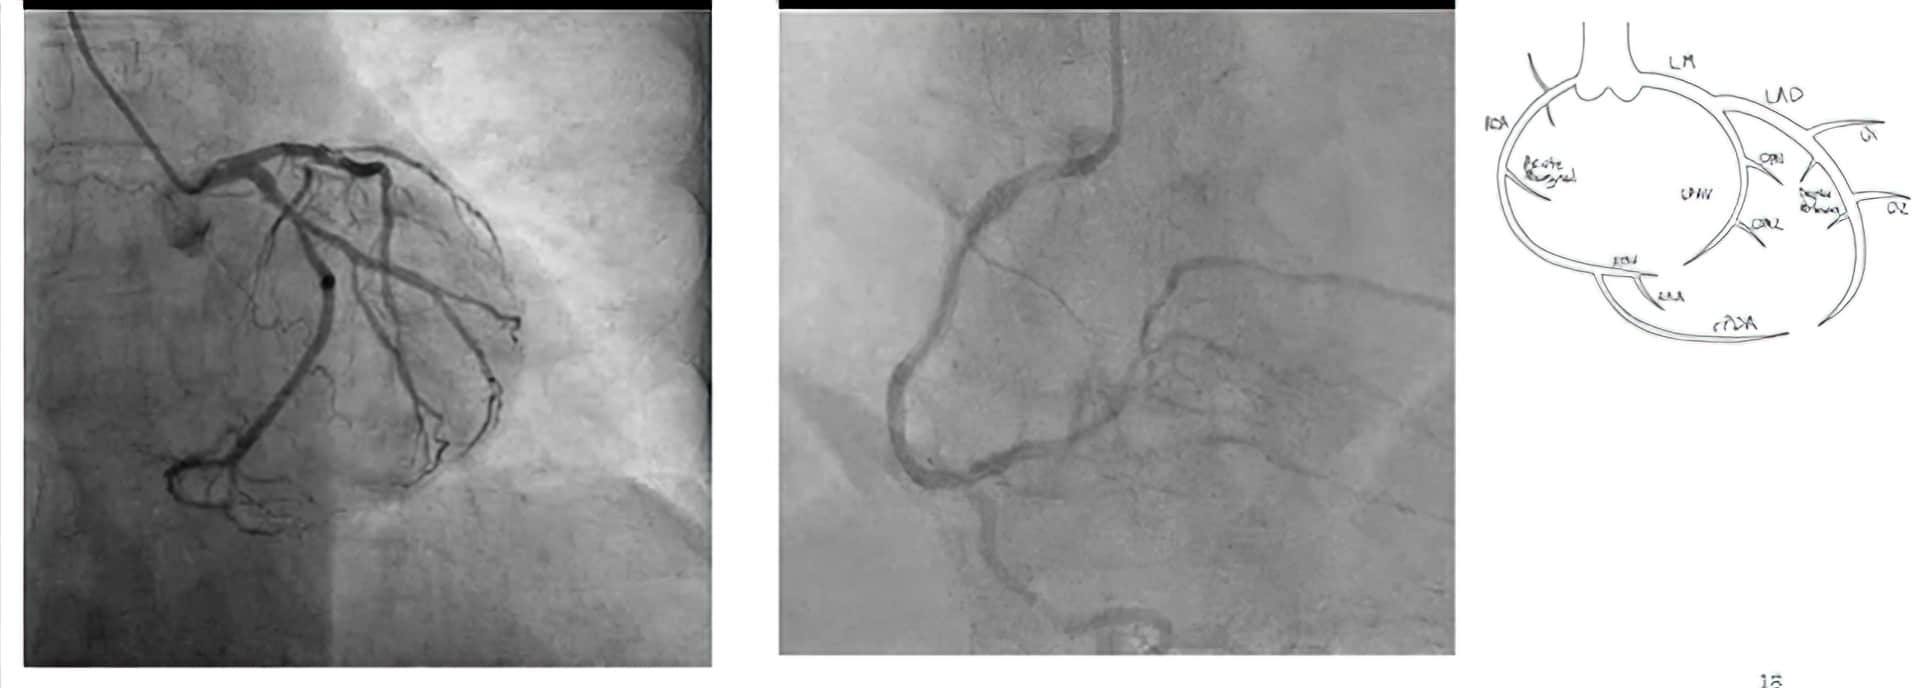

Angiografi koroner invasif (ICA)

Ini adalah metode “standar emas” yang digunakan untuk penilaian arteri koroner.

Kateter yang sangat tipis dan fleksibel dimasukkan melalui arteri radialis atau arteri femoralis. Pewarna kontras kemudian disuntikkan dengan pencitraan sinar-X untuk memvisualisasikan arteri koroner.